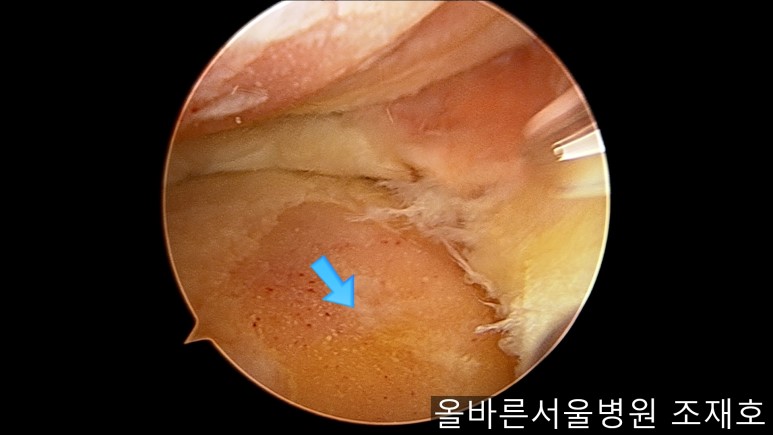

为了软骨再生,在胫骨上端进行微骨折术。

胫骨上端是通过微骨折术,可再生软骨的地方。

尽量将孔打地细密,确认此处骨髓腔内的血流出。